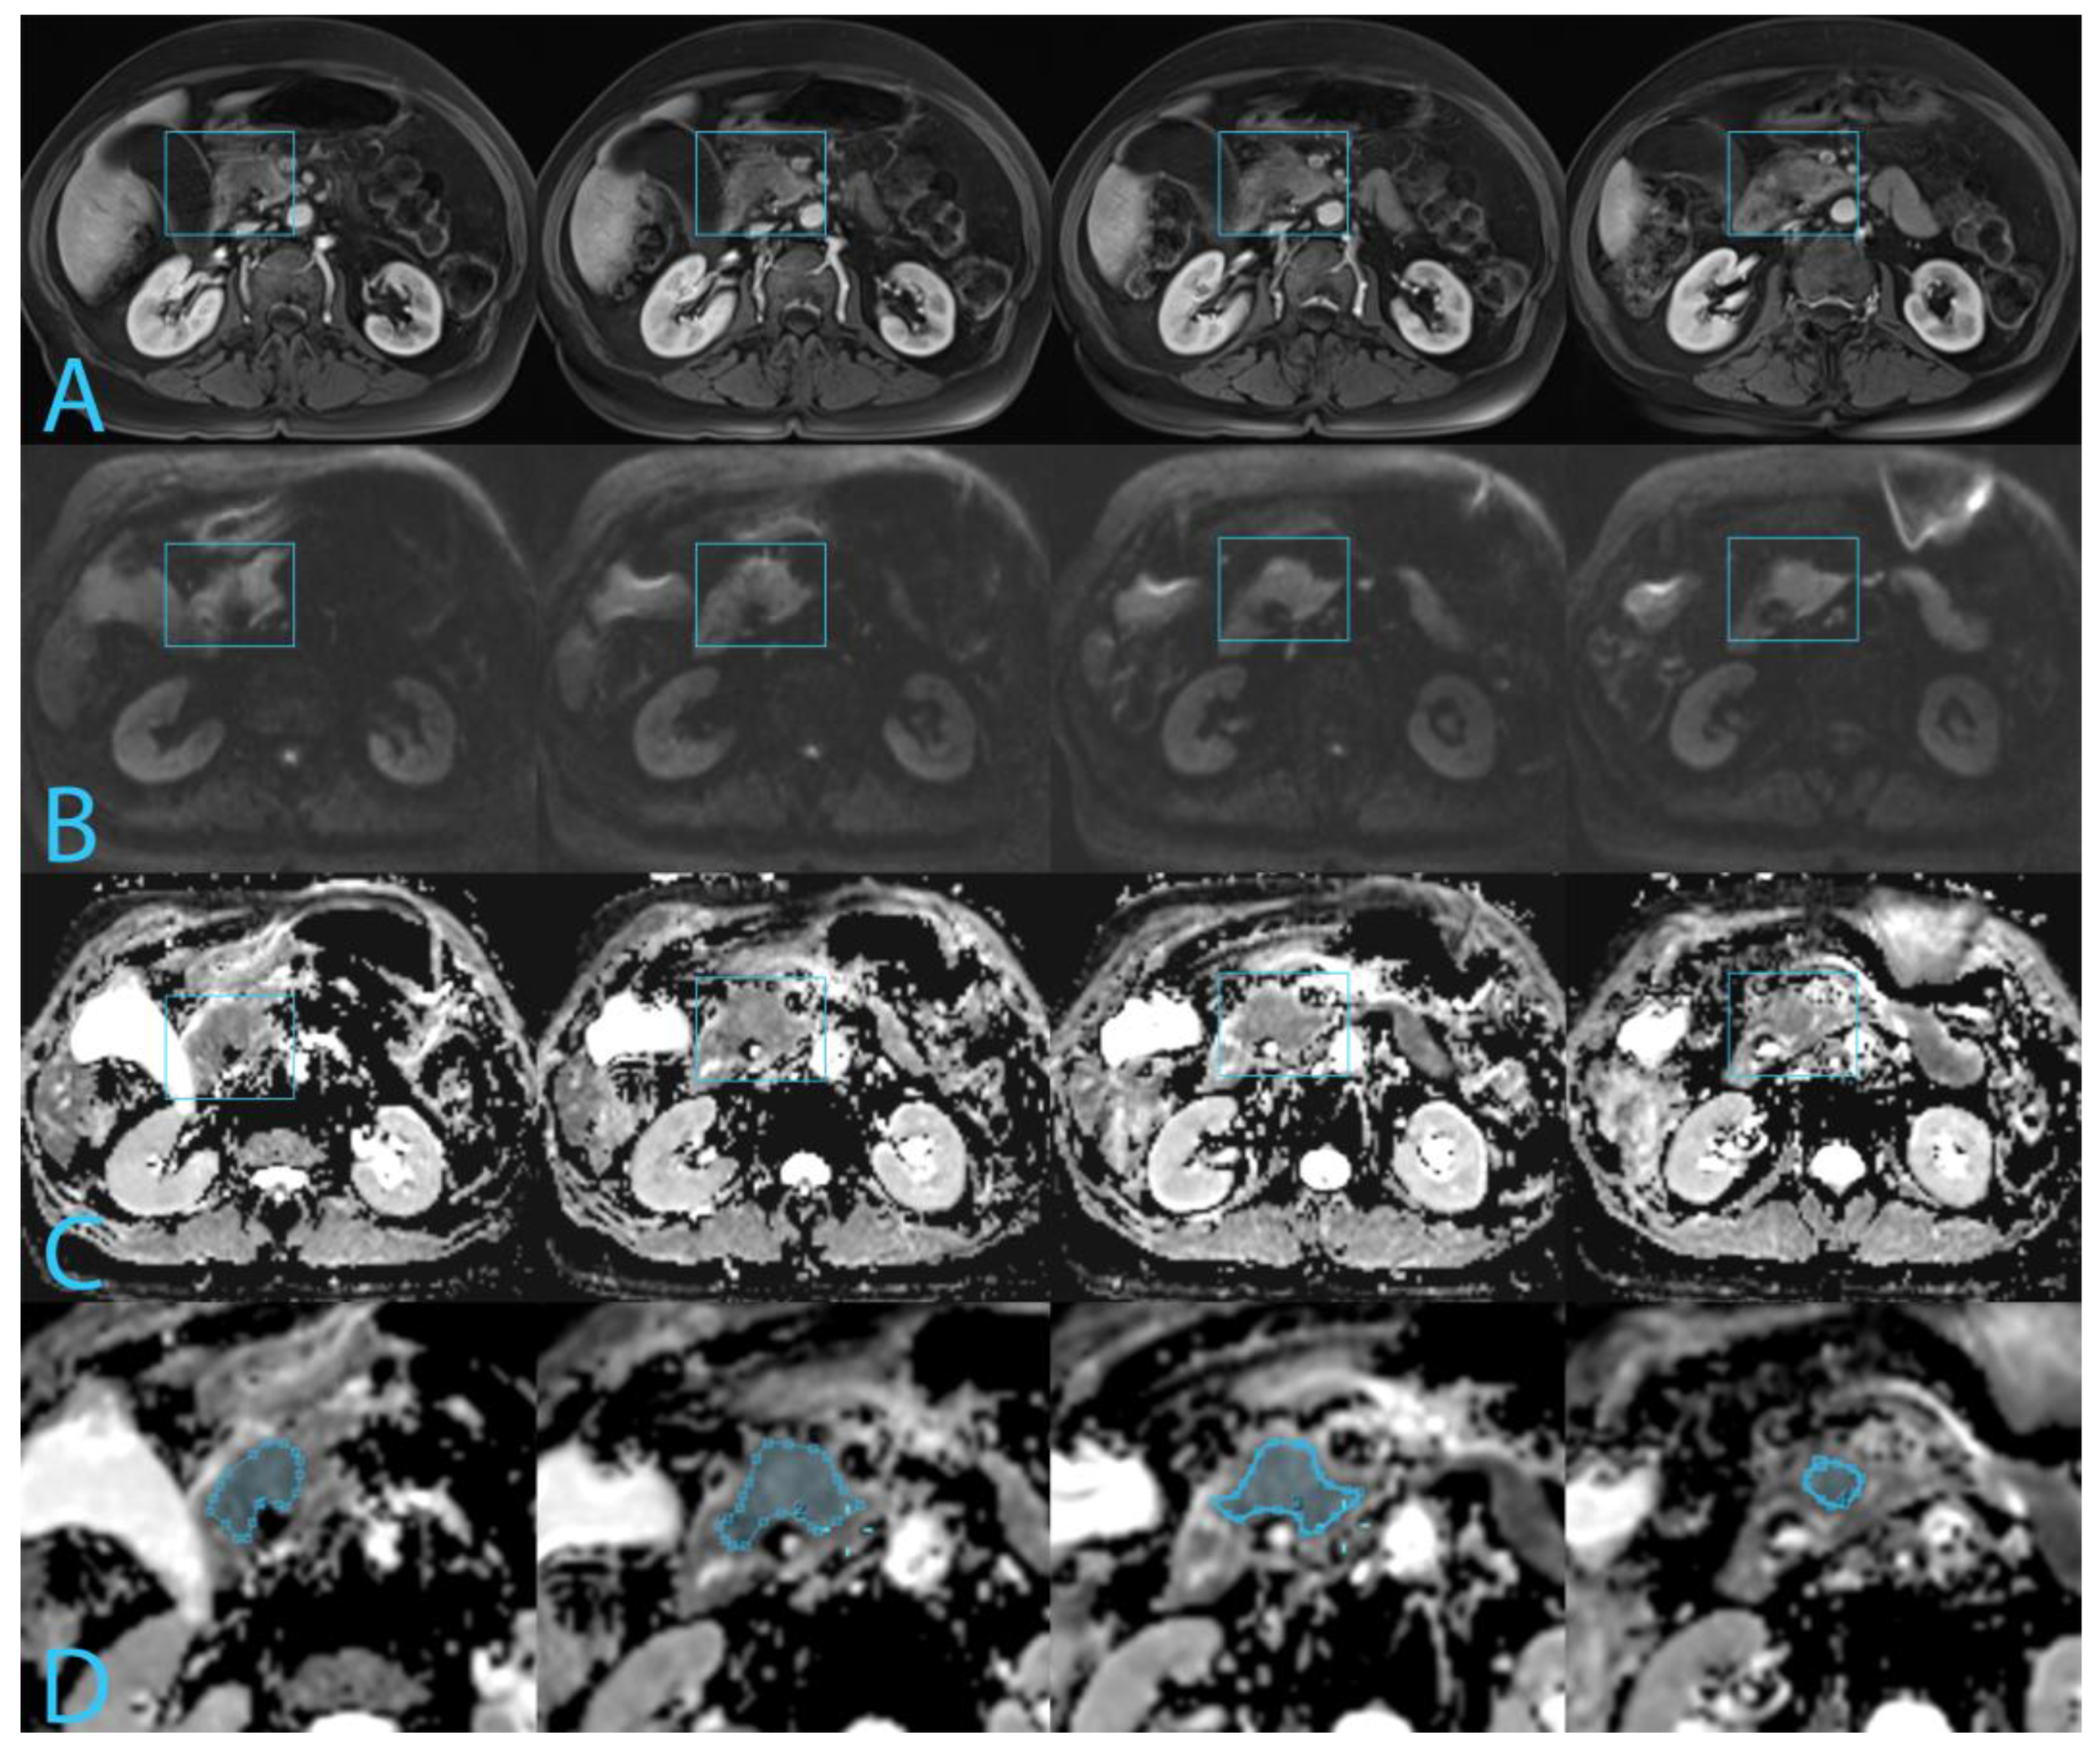

2.2. MRI Technique

2.3. Image Analysis